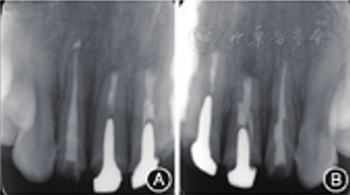

圖8 術(shù)后3個月復(fù)查患者根尖X線片 A:根尖病變明顯縮小;B:根尖病變明顯縮小